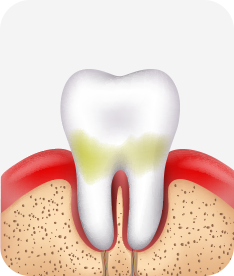

치은염 (초기~중기)

치아 주위의 잇몸이 붉게 부어 있으며, 칫솔질 등을 할 때 피가 남.

스케일링 주기의 조절이 필요할 수 있으며, 올바른 칫솔질을 시행하여야 함.